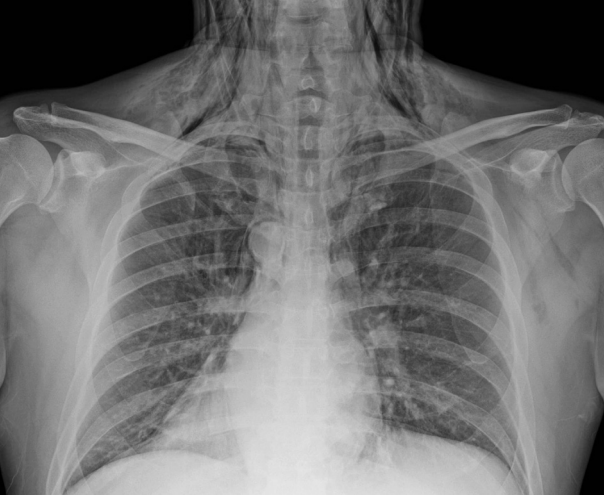

Fig. 2.

Post-operative chest anterior-posterior view findings on the day of surgery. Both cervical subcutaneous emphysema and pneumomediastinum is found.